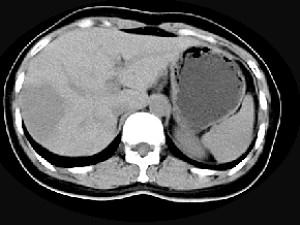

问题 女,38岁,无任何症状,体检发现肝右叶占位性病变,增强表现如图,最可能的诊断为 ( )

选项 A、肝脓肿 B、肝腺瘤 C、肝转移瘤 D、肝血管瘤 E、原发性肝癌

答案 D